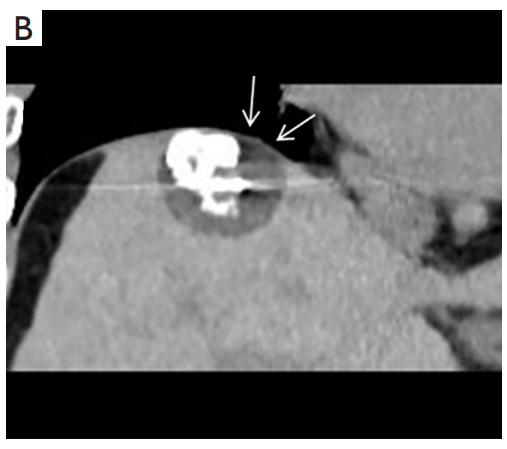

背景:肝癌是中國(guó)最常見(jiàn)的惡性腫瘤之一,發(fā)病率和死亡率都很高。雖然手術(shù)切除是最好的治療方法,但大多數(shù)患者處于晚期或直到住院才有手術(shù)指征。對(duì)于單個(gè)腫瘤直徑小于5厘米的患者,微創(chuàng)治療與手術(shù)切除效果相當(dāng);多個(gè)病灶小于3個(gè),單個(gè)病灶最大直徑小于3cm;不侵犯血管、膽管、鄰近器官和遠(yuǎn)處轉(zhuǎn)移。雖然一些傳統(tǒng)消融技術(shù)方式可以使部分患者受益,但不適用于特殊部位肝癌(定義為毗鄰大血管、肝外臟器和重要結(jié)構(gòu)的腫瘤)的治療。冷凍消融作為一種相對(duì)較新的治療方式,具有明顯的冰球效果、療效好、激活抗腫瘤免疫、并發(fā)癥發(fā)生率低等優(yōu)點(diǎn),尤其適用于特殊部位肝癌患者的治療。我們的研究目的是探討CA治療特殊部位肝癌的安全性、可行性和有效性。

① 在我們的研究中,技術(shù)成功率為100%。動(dòng)態(tài)增強(qiáng)MR檢查隨訪1個(gè)月,66例患者首次技術(shù)有效率為65例(98.5%),MR影像學(xué)未發(fā)現(xiàn)外周臟器損傷。中位隨訪時(shí)間14個(gè)月(范圍2-28個(gè)月)。高危部位肝癌局部腫瘤進(jìn)展率曲線:6、9、15和24個(gè)月的累積局部腫瘤進(jìn)展率分別為10.2%、16.5%、20.9%和30.5%。